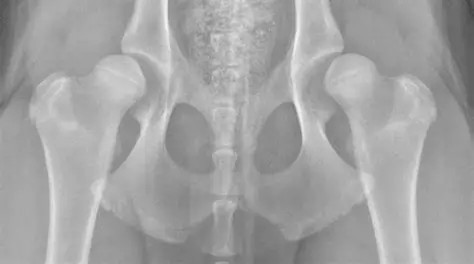

Hip Luxation

Hip luxation is the dislocation of the femoral head from the acetabulum due to trauma or a fall. Significant damage to the supporting soft tissues and sometimes the bone occurs.

The dislocation is categorized based on the direction of displacement, either craniodorsal (above the pelvis) or ventral (below the pelvis). Craniodorsal luxation is by far the most common (~90% of cases) while ventral luxation is seen more often in small breed dogs. Pets with underlying hip dysplasia are at higher risk for hip luxation because of the abnormal hip conformation.

Animals with hip luxation are typically very painful and bear little to no weight on the affected limb. The leg may appear tucked under the body or rotated abnormally when standing. Over time, mild compensation may occur, but a persistent lameness will remain because of the abnormal position of the femoral head.

Diagnosis is confirmed with radiographs of the pelvis, though the condition can often be suspected based on physical examination findings.